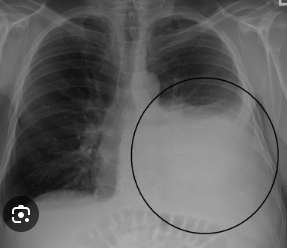

16

Q

A

Empiema Bacteriano - Staph Aureus.